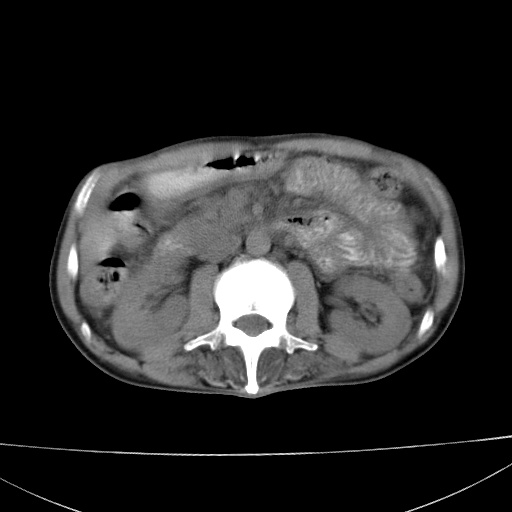

患者 男  41岁,右上腹痛伴腹泻10天,8年前有乙肝,本次b超查肝右叶占位来做ct ,请会诊!

肝硬化\\脾大\\门静脉高压,胃底静脉曲张可能性大.肝右叶肝癌肝内转移,建议增强.左侧小结石.

肝右叶肝癌肝内转移,建议增强

支持肝癌伴肝内转移,脾大,门静脉高压,胃底静脉曲张。

1)考虑肝癌;建议行ct增强扫描检查。2)脾大,门静脉高压,胃底静脉曲张。3)左肾小结石。

1)考虑肝癌及门脉瘤栓,建议行ct增强扫描检查。2)脾大,门静脉高压,胃底静脉曲张。3)左肾小结石。

结合病史;考虑肝癌。门静脉高压,脾大。胃底静脉曲张。

1)考虑肝癌;2)脾大,门静脉高压,胃底静脉曲张。3)左肾小结石。建议行ct增强扫描检查。